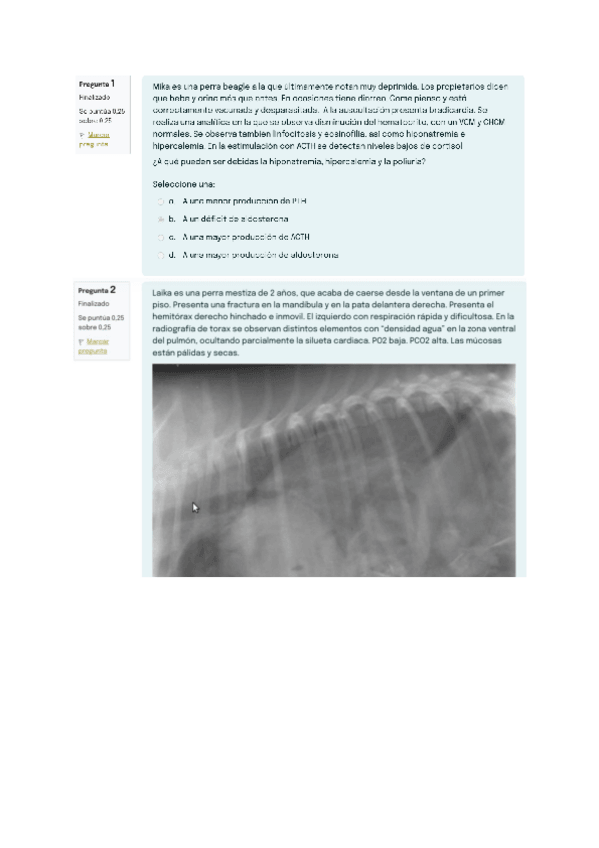

Exámenes - Examen-resuelto-junio-2023.pdf